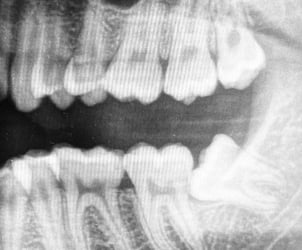

Retinuotų dantų atvėrimas ir retencinių elementų fiksacija leidžia įtraukti į dantų lanką dantis, kurie dėl vietos trūkumo ar kitų priežasčių neišdygo savarankiškai.

Atliekame visas burnos chirurgijos procedūras, įskaitant sudėtingų, neišdygusių dantų šalinimą. Ypač specializuojamės sudėtingų protinių dantų ekstrakciją, kai reikalingas chirurginis įsikišimas.